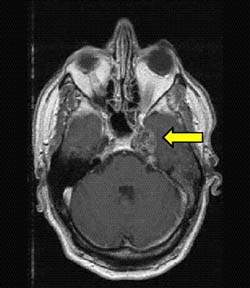

До терапии 3 месяца спустя

после ионной терапии